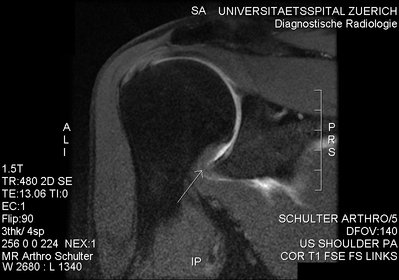

Codman introduced the term "frozen shoulder" in 1934 to describe patients who had a painful loss of shoulder motion with normal radiographic studies. In 1946, Neviasernamed the condition "adhesive capsulitis" based on the radiographic appearance with arthrography, which suggested "adhesion" of the capsule of th GH joint limiting overall joint space volume. Patients with adhesive capsulitis have a painful restriction of both active and passive GH joint motion in all planes, or a global loss of GH joint motion.

Not every stiff or painful shoulder is a frozen shoulder, and indeed there is some controversy over the criteria for diagnosing "frozen shoulder". Stiffness occurs in a variety of conditions- arthritic, rheumatic, post-traumatic, and post operative. The diagnosis of frozen shoulder is clinical resting on two characteristic features.

• Painful restriction of movement in the presence of normal x-rays, and

• a natural progression through three successive phases.

In general, a global loss of active and passive motion is present; the loss of external rotation with the arm at the patient's side is a hallmark of this condition. The loss of passive external rotation is the single most important finding on physical examination that helps to differentiate the diagnosis from a rotator cuff problem because problems of the rotator cuff generally do not result in a loss of passive external rotation.